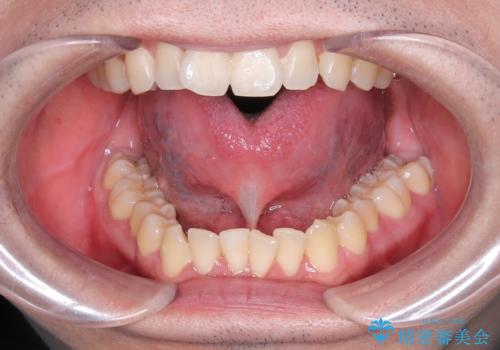

- 滑舌、舌小帯が気になるとのことで来院されました。

舌小帯の形成術を行い、舌の可動域を広げました。

舌小帯形成術は、舌の下にある小帯(舌小帯)を調整する手術です。通常、舌小帯が短い場合に行われます。この手術は、滑舌の改善や発音の向上に使用されます。